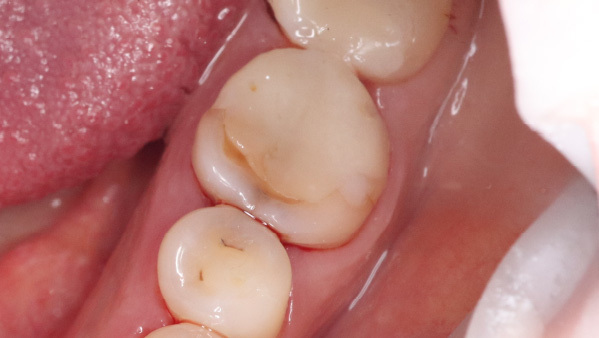

Внешне: нарушение краевого прилегания пломбы, это когда она "отклеивается" от стенки зуба и видна как желтая полоска между пломбой и зубом, а также кариозное пятно на передней поверхности. Исходя из объема пломбировочного материала, врач сразу подозревает, что ранее зуб лечился в корневых каналах, а такие зубы требуют динамического контроля и покрытия коронками. Поэтому мы начали со снимка, на котором обнаружили большую кисту.